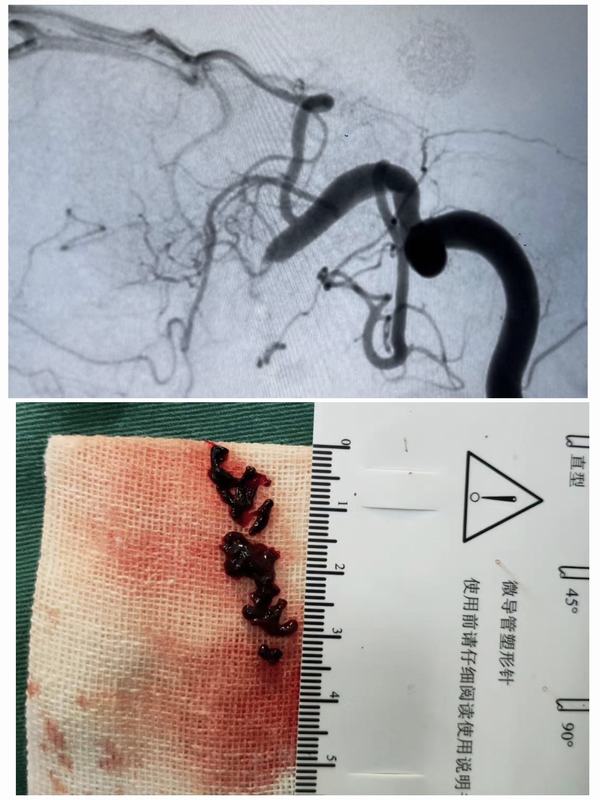

2月23日中午12:00,腦病急診科接診一名59歲女性患者,急性起病,主因:突發(fā)左側(cè)肢體無力1.6小時(shí)。經(jīng)查體患者神志清,精神差,言語不利,左側(cè)肢體肌力0級(jí)。立即開通綠色通道,急查頭顱CT示:右側(cè)基底節(jié)區(qū)及右側(cè)側(cè)腦室前角旁多發(fā)腔梗。家屬簽字同意后給予靜脈溶栓治療。12:20患者進(jìn)入導(dǎo)管室行全腦血管造影+動(dòng)脈溶栓術(shù)+機(jī)械取栓術(shù)。患者于3月3日出院,出院時(shí)患者神志清,精神狀態(tài)良好,左側(cè)肢體肌力正常、言語清晰,入院時(shí)癥狀得到完全緩解。

腦卒中具有高發(fā)病率、高致殘率、高死亡率、高復(fù)發(fā)率的特點(diǎn),給社會(huì)、家庭帶來了沉重的負(fù)擔(dān),但只要4.5-6小時(shí)內(nèi)進(jìn)行靜脈溶栓,必要時(shí)動(dòng)脈取栓的積極治療,多可獲得更好的療效。

延安大學(xué)咸陽醫(yī)院是被國家衛(wèi)健委腦防辦授牌為“高級(jí)卒中中心”單位,腦病急診科一直以來不斷開展卒中適宜新舉措、新技術(shù),在宋波主任的帶領(lǐng)下,不斷加強(qiáng)動(dòng)靜脈溶栓、介入取栓方面技術(shù),為卒中患者提供最優(yōu)救治流程和最佳診療方案,有效縮短救治時(shí)間,切實(shí)改善患者預(yù)后,降低卒中患者致死致、殘率及再發(fā)率,為腦卒中患者打通了一條真正意義上的“生命通道”。